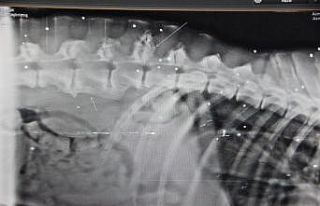

Alerjik rinitte burunda tıkanıklık, akıntı, hapşırık, geniz akıntısı, burun kaşıntısı, gözlerde yaşarma, kaşıntı ve kızarıklık oluşabilir iken akciğerde ise sekresyon artışı, öksürük, hırıltılı solunum ve nefes darlığı gibi belirtiler olduğunu ifade eden Opr. Dr. Yusuf Şentürk, “Bu belirtiler Kovid-19 başta olmak üzere viral üst solunum yolu enfeksiyonlarında da görülebileceğinden alerjik rinit ile karıştırılabilir. Kovid-19’da ise boğaz ağrısı, kuru öksürük, titreme, halsizlik, kas ve eklem ağrısı, tat-koku kaybı ve özellikle yüksek ateş olurken, bazen burun tıkanıklığı ve akıntı oluşabilir. Ancak alerjik rinitteki gibi hapşırık ve burun kaşıntısı olmaz, ayrıca alerjik rinitte ateş gözlenmez. Alerjik rinitte alerji testleri yapılarak alerjenin belirlenmesi önemlidir. Kovid-19 ise nazofarengeal sürüntü testi ile tanılanır” şeklinde konuştu.